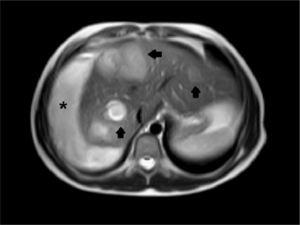

Hallazgos de imagenEn la ecografía se apreciaban múltiples lesiones hepáticas de baja ecogenicidad (fig. 1), sin flujo detectable en el estudio Doppler, y una imagen hipoecoica perihepática, con ecos internos, que se orientó como hematoma (fig. 2). En la RM algunas de las lesiones mostraban elevada intensidad en secuencias potenciadas en T1 y todas brillaban en secuencias potenciadas en T2, con realce inespecífico (fig. 3). El hematoma se comportaba de forma heterogénea aunque era hiperintenso en todas las secuencias (fig. 4).

El aspecto radiológico de estas lesiones varía en función de la cantidad de sangre no coagulada que hay en ellas y su flujo. Ecográficamente suelen ser hipoecoicas respecto al resto del parénquima, excepto cuando se complican con hemorragia, mostrando entonces focos de mayor ecogenicidad.No suelen mostrar flujo en el estudio Doppler. En la TC son lesiones hipoatenuantes, aunque pueden presentar densidad aumentada si han sangrado o mostrar calcificaciones en su interior4. Si las cavidades pelióticas son menores de 1cm el estudio puede ser normal. Como presentación inusual pueden tener niveles líquido-líquido por sangrado5. Su comportamiento tras la inyección de contraste es variable. Clásicamente se ha descrito el «signo de la diana» que consiste en un realce nodular central en fase arterial, que sigue un sentido centrífugo en fases posteriores6. En general, pueden o no tener realce progresivo y éste ser centrífugo o centrípeto7. En RM los hallazgos visualizados también varían según la edad y fase de sangrado de las lesiones, lo que traduce su variable aspecto en T1. En secuencias potenciadas en T2 son de intensidad elevada8. En la difusión, los valores de ADC de las lesiones son menores que en el parénquima sano, probablemente debido a la presencia de trombosis y hemorragia5.